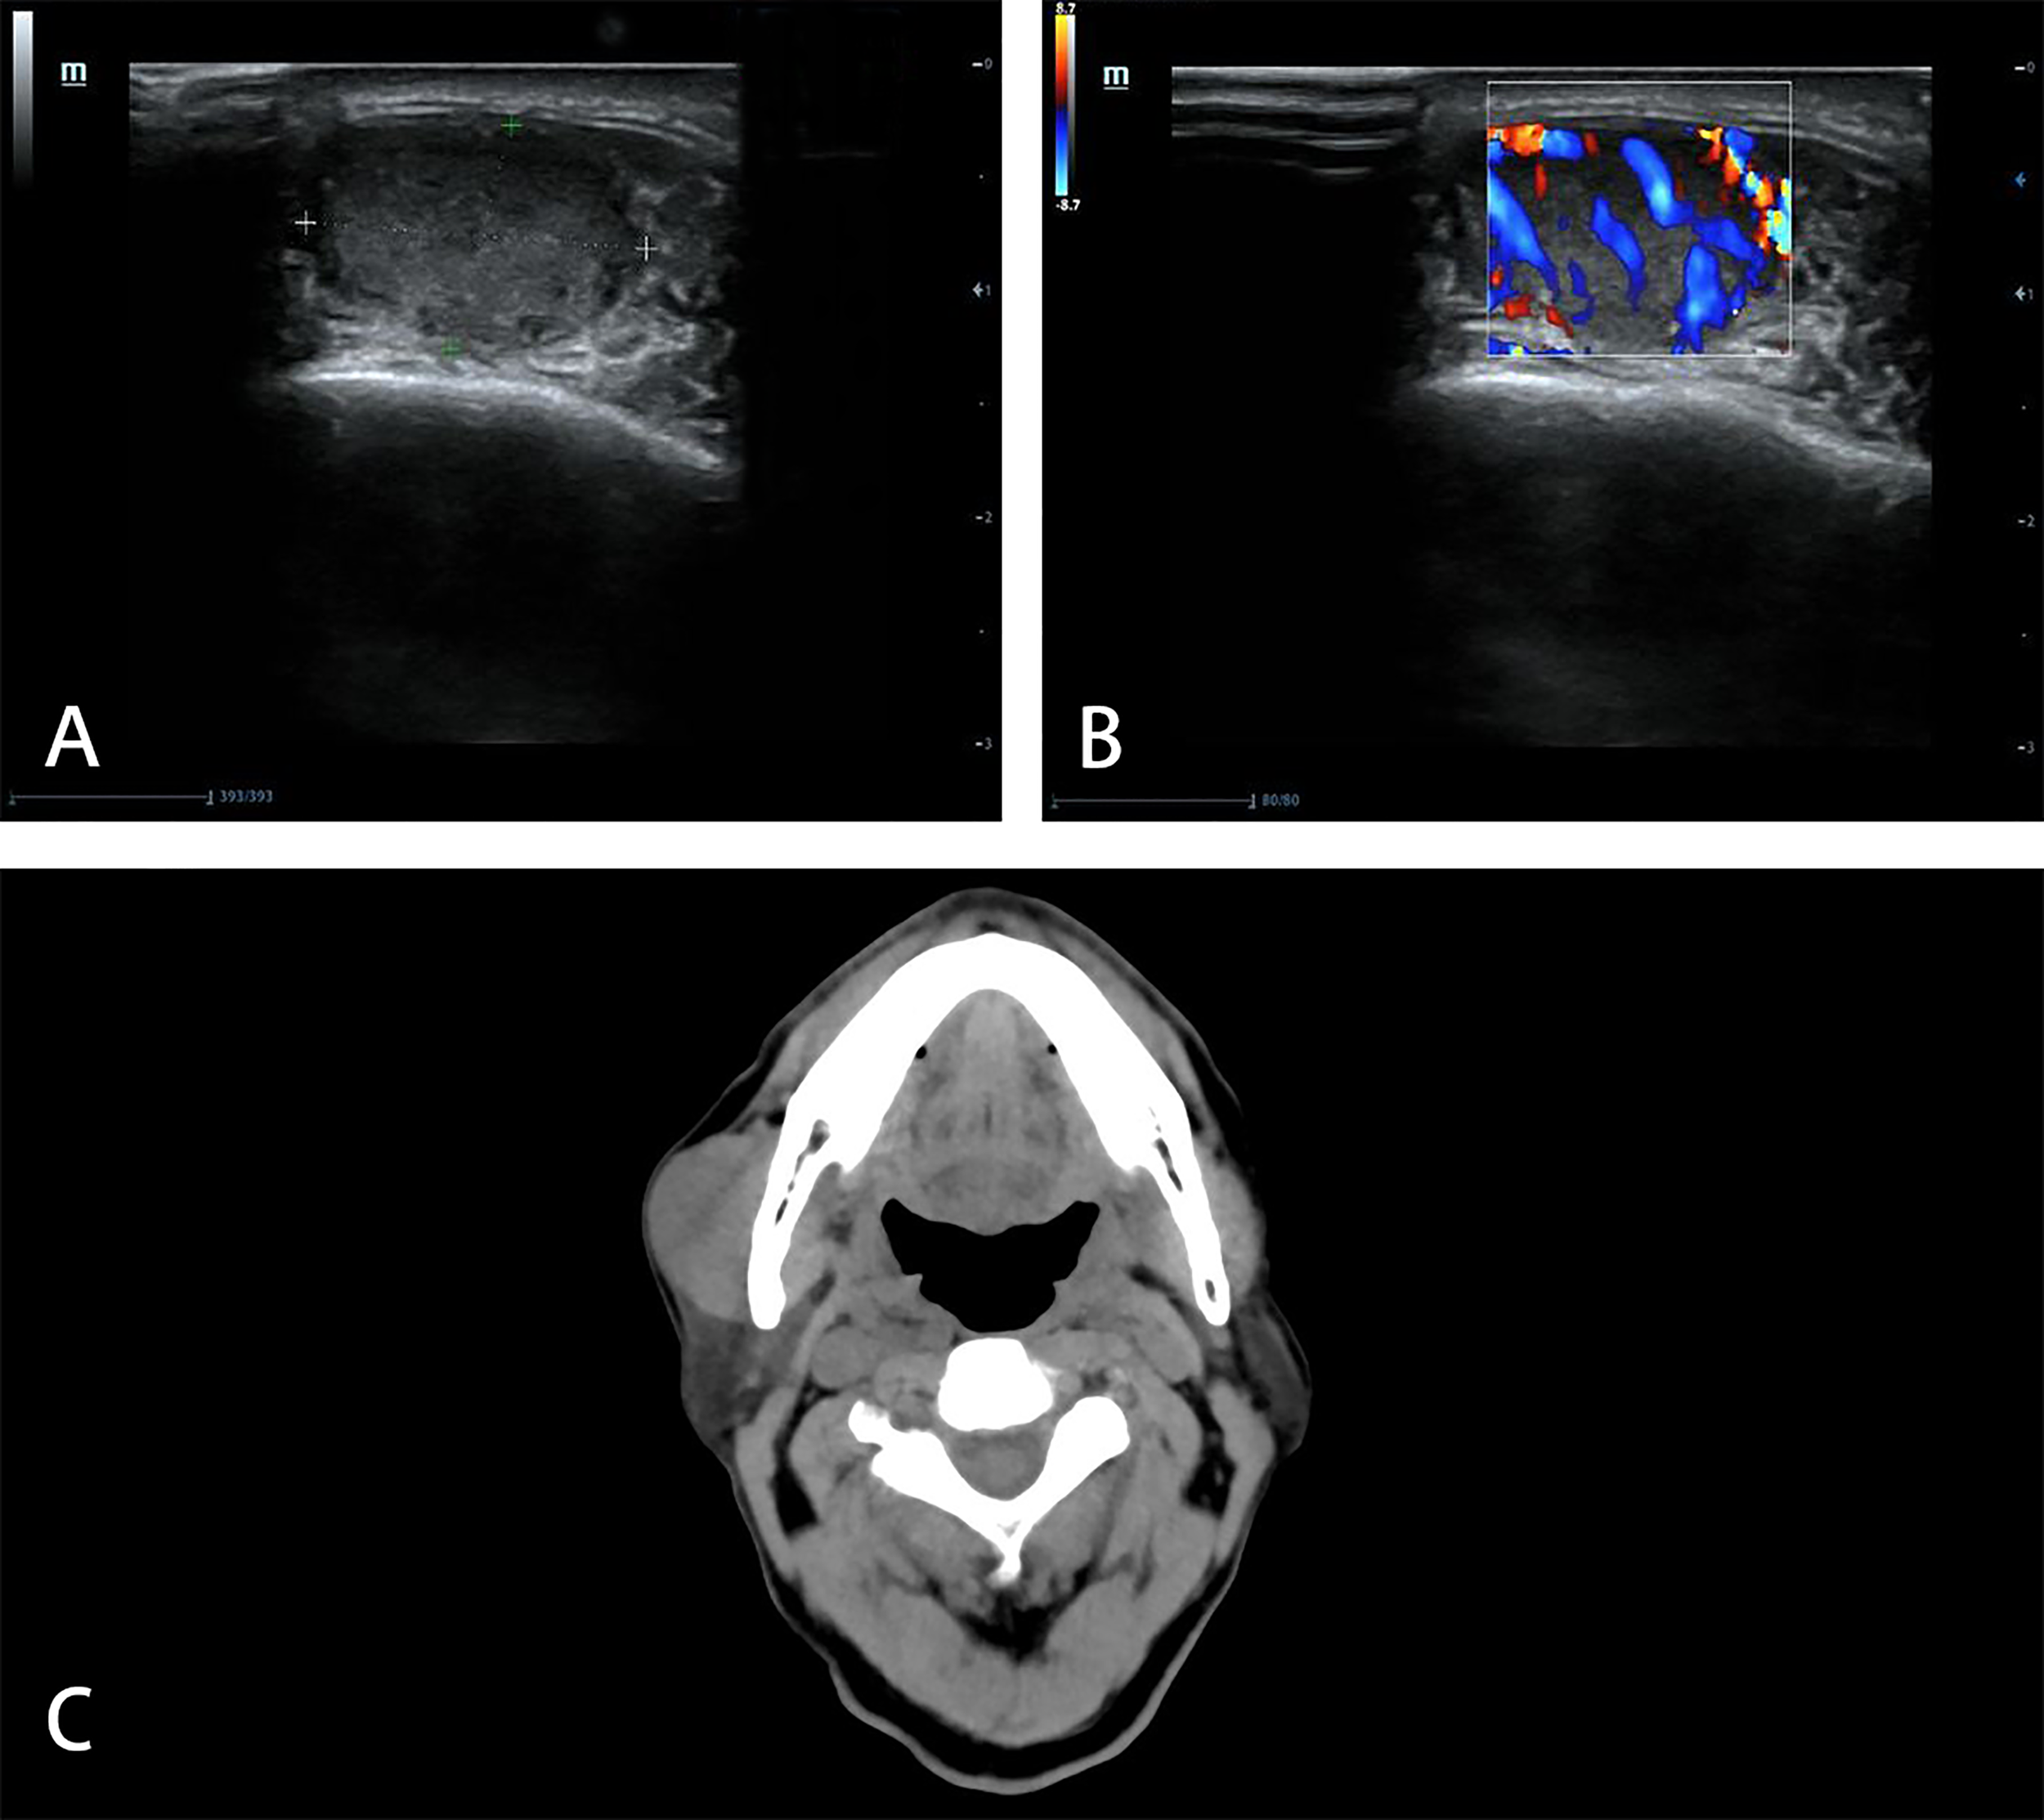

A 76-year-old male was hospitalized in our hospital due to asthma in July 2019 and found a mass in the right masseter area without symptoms. Ultrasonography (US) showed a mass of 17 mm × 17 mm × 10 mm which could be detected in the muscle layer of the masseter area, with hypoechogenicity, clear boundary and high vascularity (Figure 1). A diagnosis of “fibroma” was made. The patient chose close follow-up rather than any treatment, because of concomitant asthma and painless mass.

Figure 1

Imaging manifestations of masseter muscle metastasis in US and CT. US shows a hypoechoic (A), hypervascular (B) mass in the muscle layer of the masseter area in 2019. CT shows unclear boundary between the mass and right masseter muscle in 2021 (C).

The mass increased gradually, so he went to our hospital in June 2021. In the area of masseter muscle, a round protrusion with a diameter of 3 cm was touched and local skin was complete. It was a little tough in texture, with no tenderness and poor mobility. Computed tomography (CT) demonstrated that the solitary mass of 38.4 mm × 22.3 mm existed at the surface of masseter muscle and the boundary with the masseter muscle was unclear (Figure 1). There was no other mass found in CT.